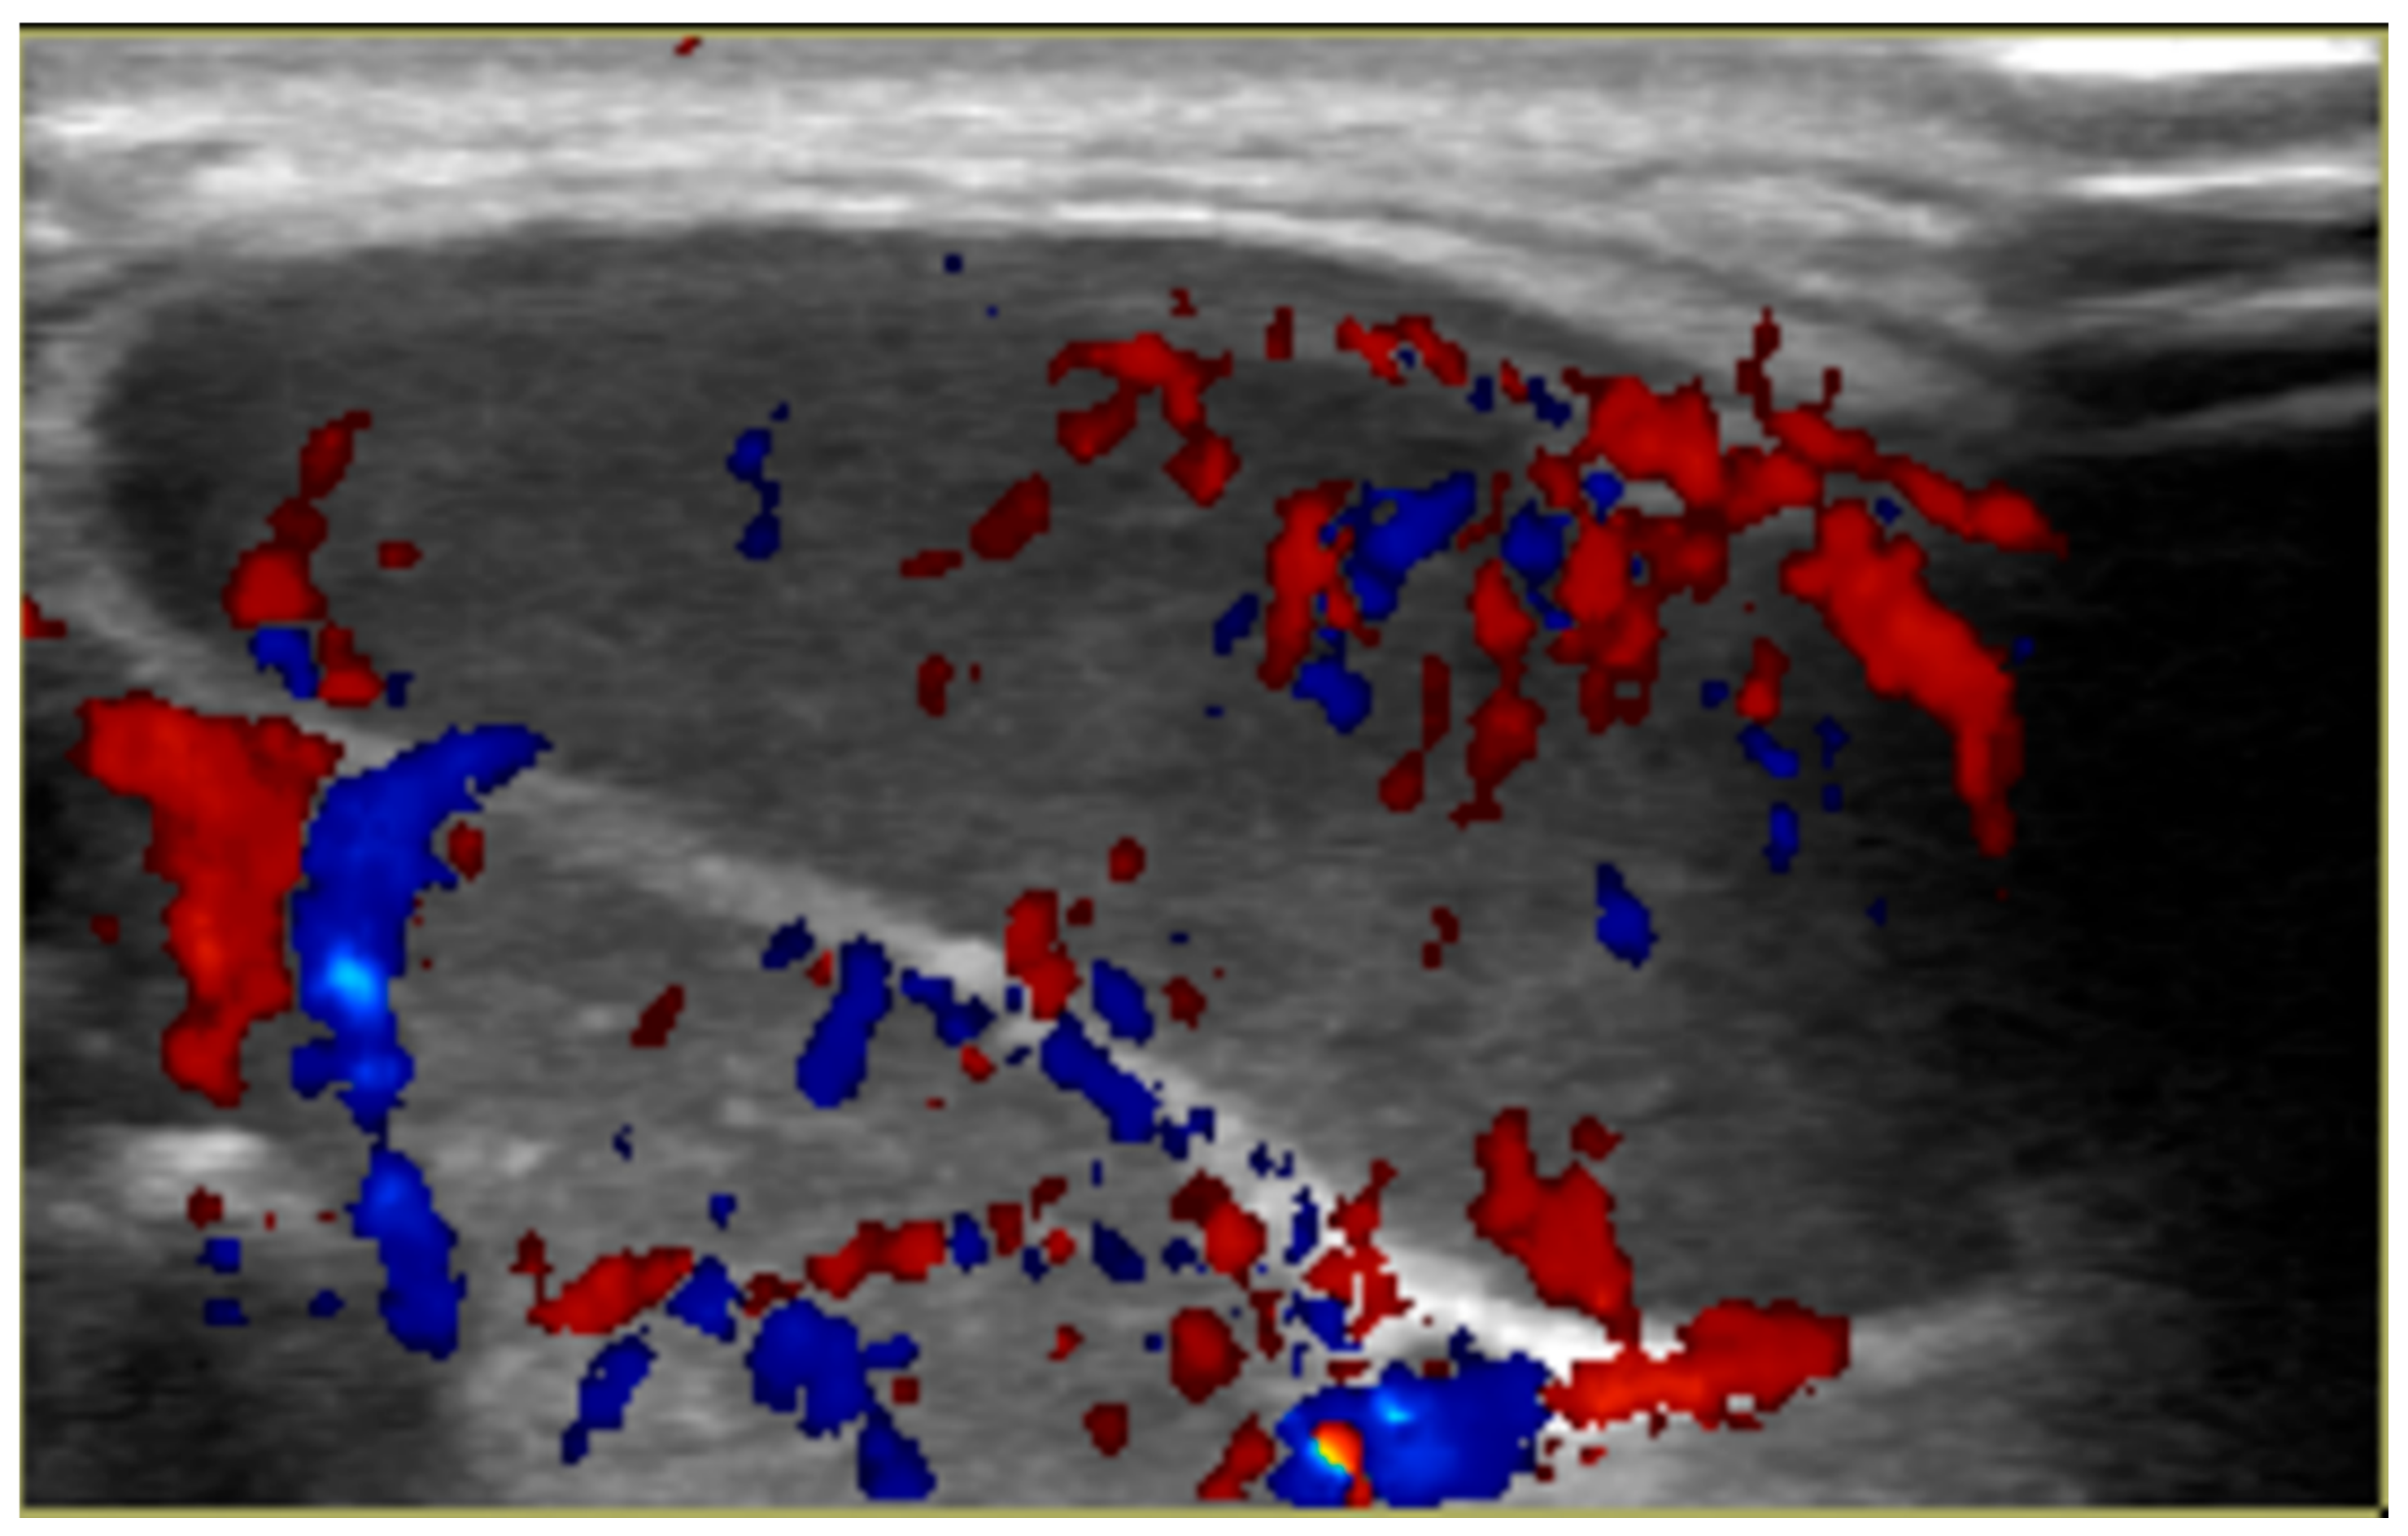

2. Case Report